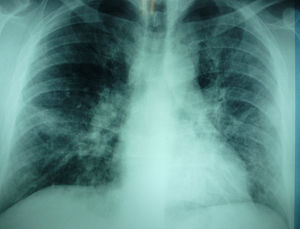

Un hombre de 39 años (gran fumador, hipertenso y moderadamente obeso) acudió a la Unidad Interna de Atención en octubre de 2012 por un cuadro de disnea de 3 días de evolución con tos productiva paroxística y dolor retroesternal, sin fiebre. Se detectaron crepitaciones leves al final de la espiración en los campos pulmonares medios y bajos de forma bilateral, asociadas a una fase espiratoria medianamente prolongada y leucocitosis leve. El paciente rechazó el ingreso hospitalario y 2 días más tarde regresó por agravamiento de una intensa disnea en reposo, con frecuencia cardiaca de 130 latidos por minuto y fiebre (38,5°C). Una nueva radiografía de tórax reveló infiltrados alveolares más intensos, difusos y extendidos por todo el pulmón izquierdo y el campo medio del pulmón derecho (fig. 1). En el análisis rutinario de sangre se halló leucocitosis, aumento de neutrófilos y monocitos, aumento relativo de PCR (7,5mg/dl), VSG (73mm/h), ALT (83U/L) y LDH (484U/L).